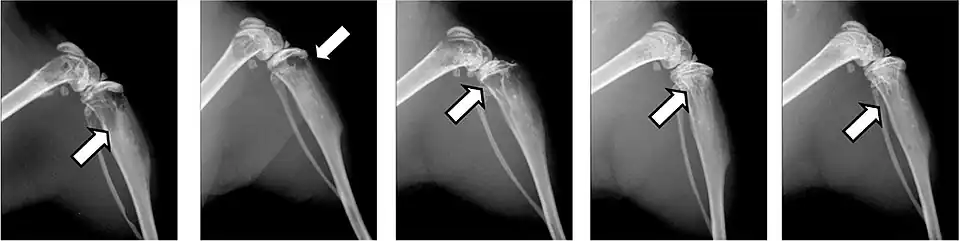

Pathologische Frakturen

Seltener wird eine Knochenmetastase durch eine pathologische Fraktur erstmals symptomatisch.[27]:11[74]

Pathologische Frakturen sind Knochenbrüche, die ohne äußere Einwirkungen aufgrund einer erkrankungsbedingten Schwächung der Knochenmatrix entstehen. Vor allem osteolytische, aber auch osteoplastische Knochenmetastasen schwächen den betroffenen Knochen, der dann unter Umständen schon durch leichte mechanische Belastungen überfordert ist und bricht. Diese Brüche können unter alltäglichen Situationen, wie beispielsweise dem Aufrichten aus einem Sessel oder dem Umlagern eines Patienten, auftreten.[75] Bei den osteoplastischen Knochenmetastasen ist zwar die Knochendichte erhöht, die Knochenfestigkeit ist aber durch den völlig unstrukturierten Aufbau herabgesetzt.[6] Im Bereich der Wirbelsäule können sie zu Versteifungen führen.[64]

Pathologische Frakturen führen zu weitreichenden Komplikationen und haben einen erheblichen Einfluss auf die Lebensqualität sowie die Prognose. Die mittlere Lebenserwartung kann um mehrere Monate sinken.[22] Mit Bisphosphonaten lässt sich diese Form von Knochenbrüchen in vielen Fällen vermeiden.[76][77]

Von Knochenbrüchen sind meist die Rippen oder Wirbelkörper betroffen. Brüche in den langen Röhrenknochen, insbesondere am Hals des Oberschenkelknochens („Oberschenkelhalsbruch“), haben eine besonders hohe Morbidität und sind der Hauptgrund für eine chirurgische Versorgung. Frakturen an Wirbelkörpern können zu spinalen Kompressionssyndromen führen.[64]

- Aufnahmen pathologischer Frakturen

-

Pathologische Fraktur des Oberarmknochens bei einer Metastase eines Nierenzellkarzinoms -

Pathologische Fraktur des linken Oberarms bei Knochenmetastase einer Patientin mit Brustkrebs -